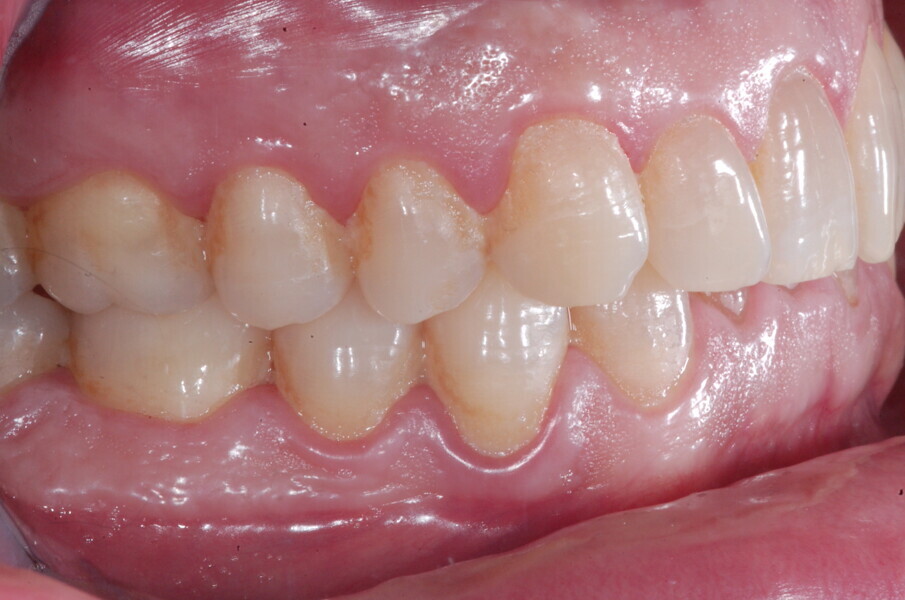

À la fin du traitement, on pouvait observer une relation de classe I des canines et des molaires, une légère augmentation de l’inclinaison des incisives supérieures (Ui-FH = 112°), une correction complète de l’inclinaison des incisives inférieures (IMPA = 97,09°) grâce à la vestibulo-version, et une légère amélioration de l’hypodivergence (SN-GoGn = 27°) résultant de l’extrusion relative des dents postérieures, et de l’utilisation d’élastiques de classe II — petite variation (1°) très intéressante compte tenu de l’âge du patient (Figs. 25–35). La ligne du sourire était harmonieuse et correspondait à une relation idéale entre les incisives supérieures et la lèvre inférieure. Le sourire avait été élargi grâce au contrôle du torque des segments latéraux et postérieurs.

Lors du suivi à un an, alors que le patient portait un appareil de rétention (appareil de rétention Vivera avec rampes d’occlusion, Align Technology), le résultat était stable et l’intercuspation était nettement meilleure (Figs. 38–42).